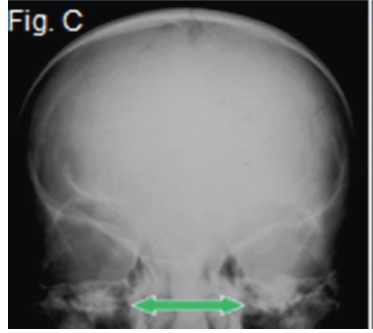

A diagnosis of frontonasal malformation was made. Frontonasal malformation has been defined as a combination of two or more of the following characteristics: hypertelorism, broadened nasal bridge, medium facial cleft affecting the nose and the upper lip and sometimes the palate, unilateral or bilateral clefting of the nasal alae, lack of formation of the nasal tip. The appearance of cranium bifidum (also known as cleft skull or enlarged parietal foramina) is characterized by the unsuccessful midline migration of the cranial vault, and a V-shaped hairline prolongation onto the middle of the forehead. The clinical picture (Fig. A) shows many of the characteristics mentioned above. The postero-anterior view of frontonasal malformation (Fig.B) shows hypertelorism, a widened nasal bridge and persistence of the metopic suture (arrow). A further postero-anterior view (Fig. C) shows persistence of the anterior fontanelle and a widened nasal bridge (arrow) with concomitant hypertelorism. The Waters view (Fig.D) demonstrates the hypoplastic maxillary sinuses. There is also marked hypertelorism and a widened nasal bridge.